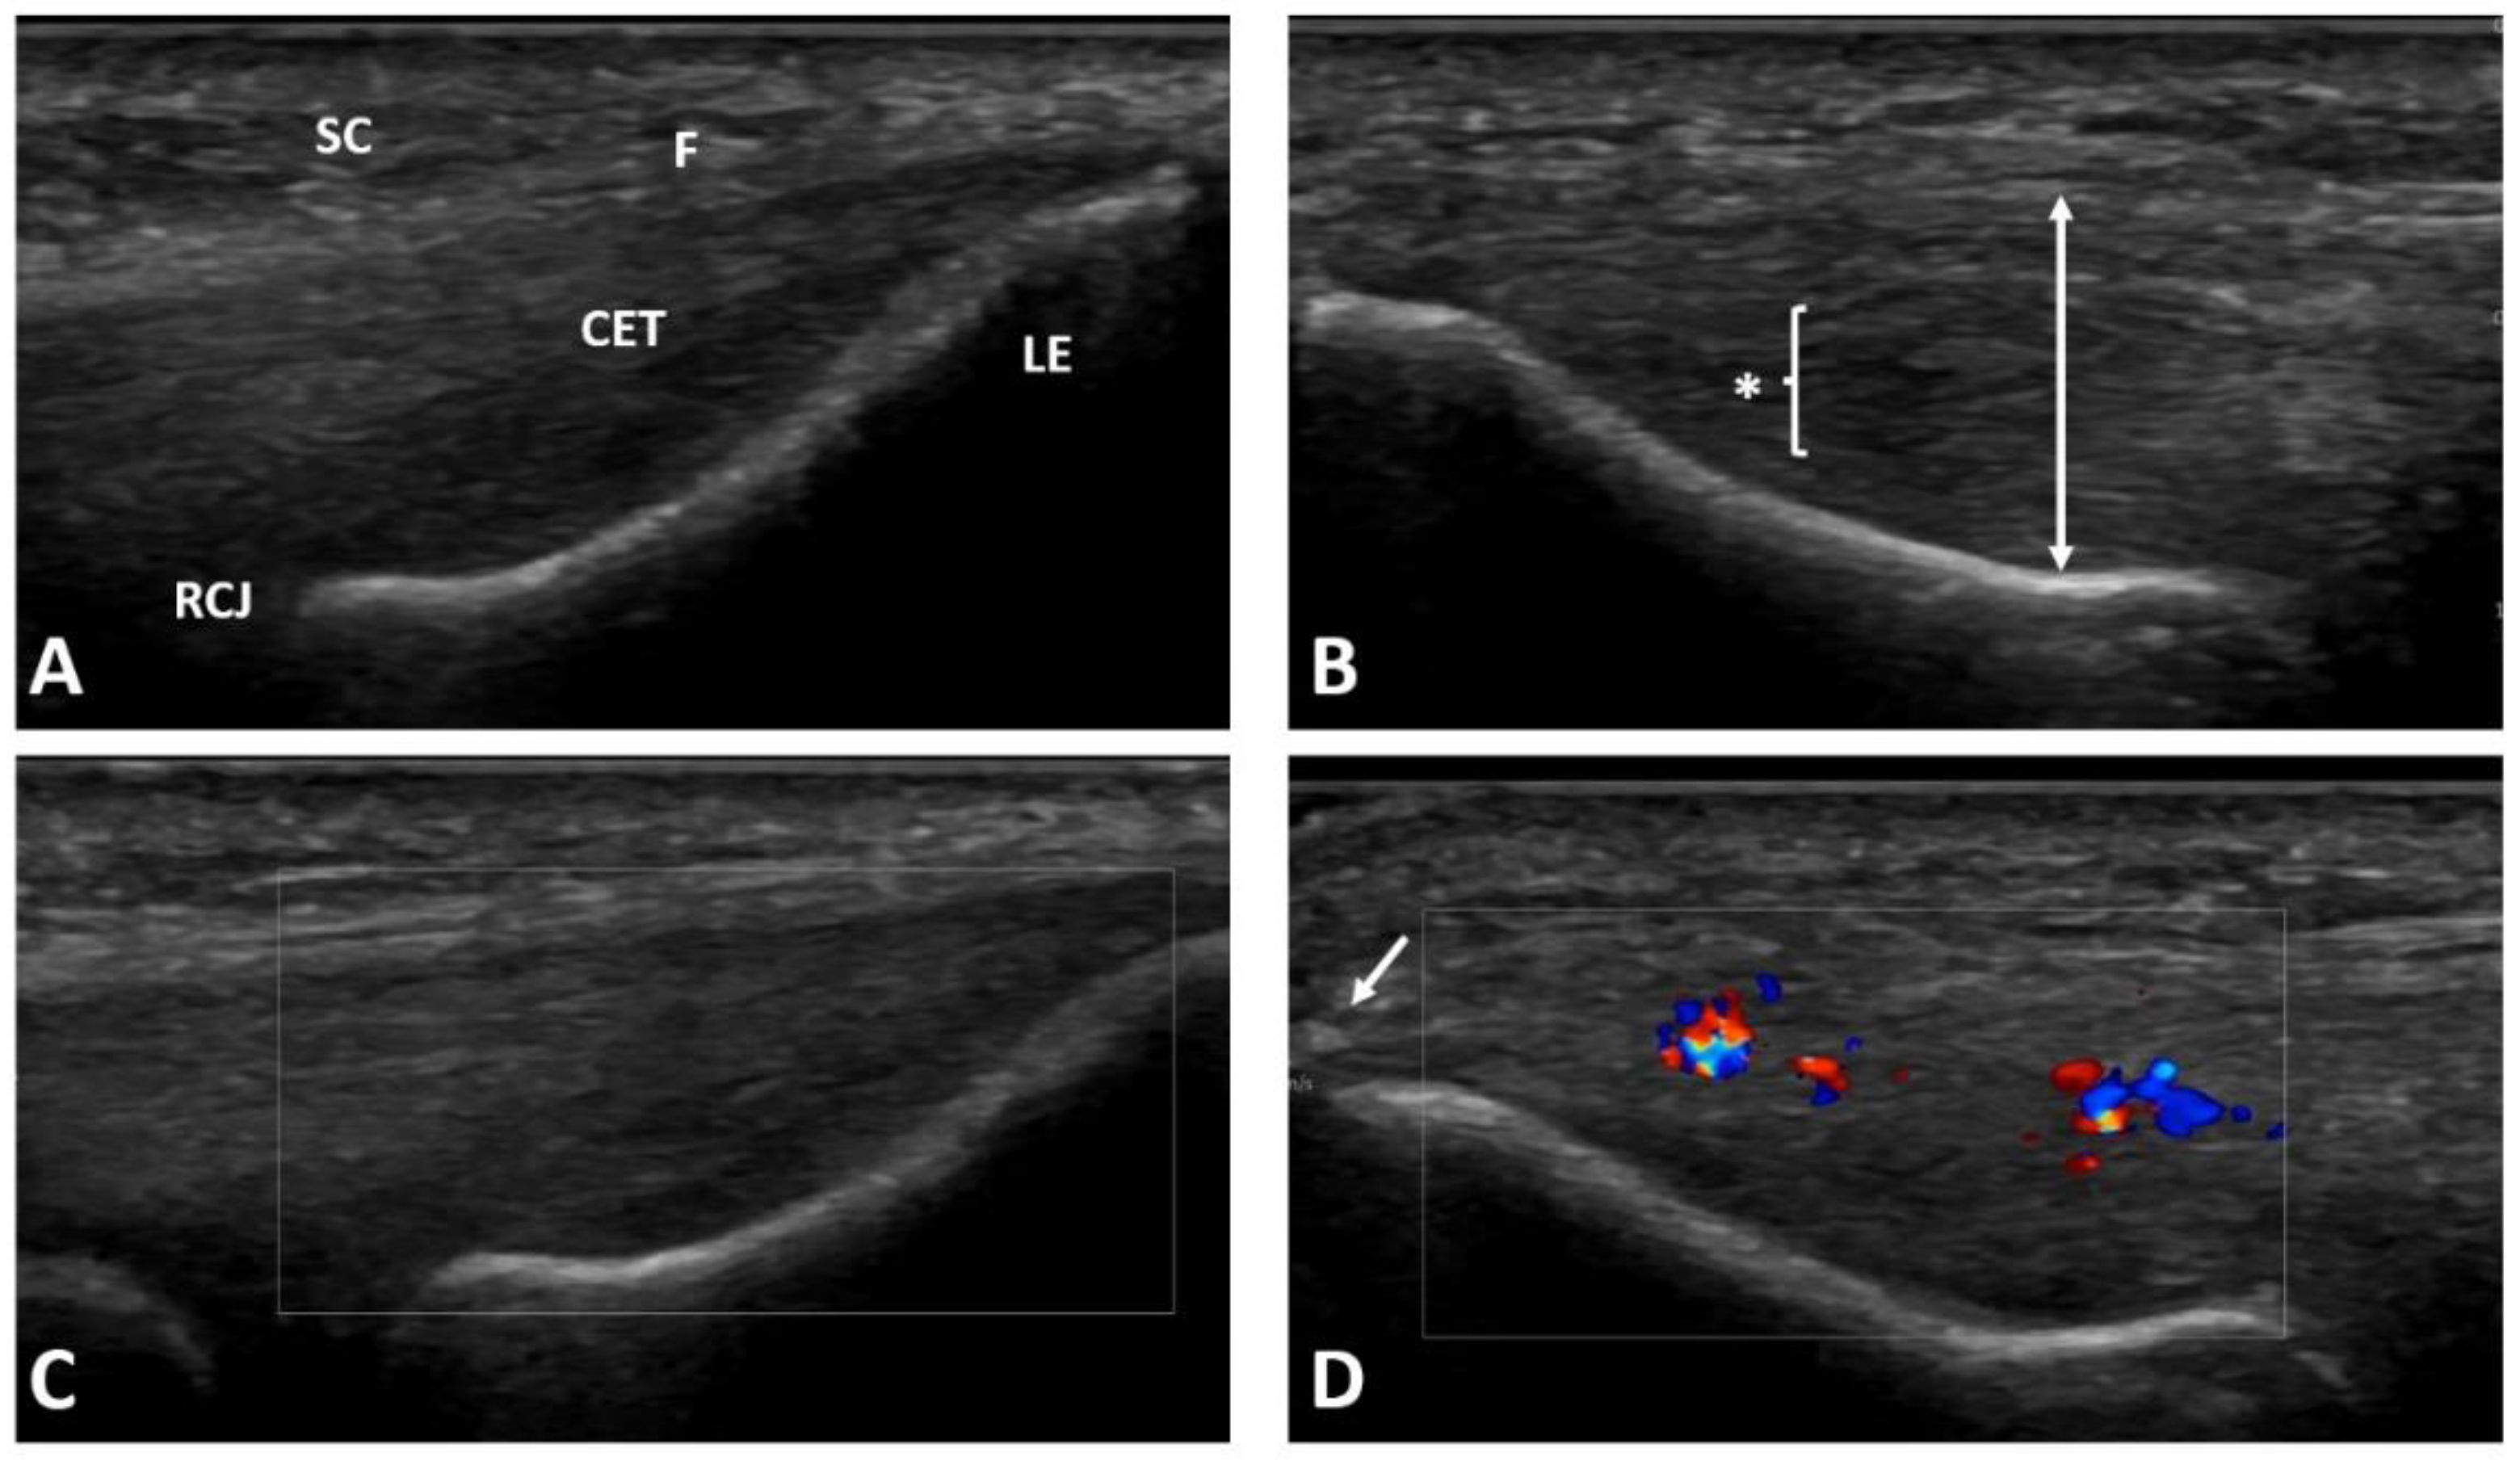

We enrolled patients with pain on the lateral side of the elbow joint after the failure of first line treatment for at least three months, with confirmation of lateral elbow enthesopathy in at least one provocative test (the Cozen’s test, Thomson’s test, Maudsley’s test, or Chair test) [1]. Patients with previous invasive treatment on the lateral aspect of the involved elbow (including previous injections), with hematological diseases, diabetes, gout, malignant tumors, advanced osteoarthritis of the elbow joint, nervous system diseases related to the upper limb, suspicion of an infectious process, who were pregnant, or taking medications that may affected platelet function or the coagulation system were excluded from the study. The patients learned about the possibility of taking part in the study from the University’s website and social media and during a visit at an outpatient clinic. If they volunteered to participate in the study, they were recruited after meeting the inclusion criteria at the initial visit. A bilateral X-ray of the elbow and ultrasound examination were performed to exclude other pathologies and to confirm changes typical for lateral elbow enthesopathy (see Figure 1) [21]. Information about the patients’ age, height, and weight (for body mass index, BMI calculation), type of work, duration of symptoms, smoking status, sports activity, medications, any other diseases, and previous treatments were collected during a medical interview.

Figure 1.

Ultrasound examination of the patient’s both elbows for lateral elbow tendinopathy confirmation: (A) healthy lateral epicondyle region of the contralateral elbow; (B) pathological common extensor tendon thickening and region with diffuse hypoechogenicity typical for lateral elbow tendinopathy; (C) healthy common extensor tendon without activity in color Doppler; (D) neoangiogenesis shown as increased activity in color Doppler in the tendinopathic region. SC—subcutaneous tissue; F—fascia; CET—common extensor tendon; LE—lateral epicondyle; RCJ—radiocapitellar joint; * and bracket—diffuse hypoechogenic region; two-head arrow—tendon thickness measurement; arrow—enthesophyte.